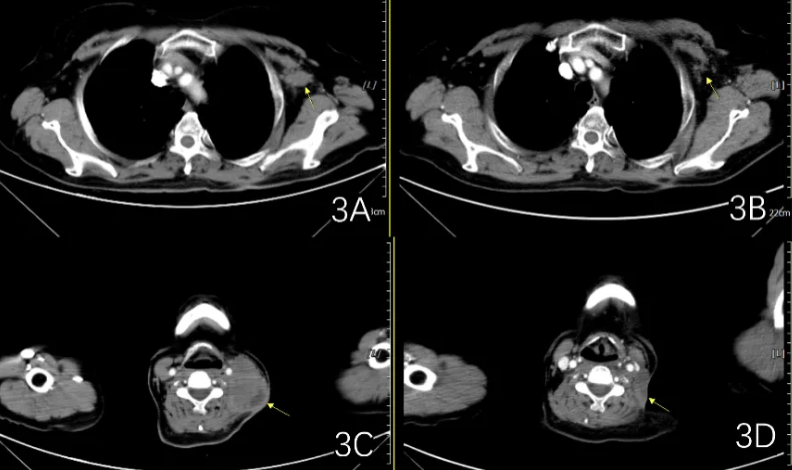

图4 一线治疗2周期后疗效评估为大PR(左:2019-11-7;右:2019-12-25)

图5 一线治疗后进展(左:2020-7-27;右:2021-3-15)

图9 CT评估示病灶明显缩小(左:2022-7-17;右:2022-12-6)